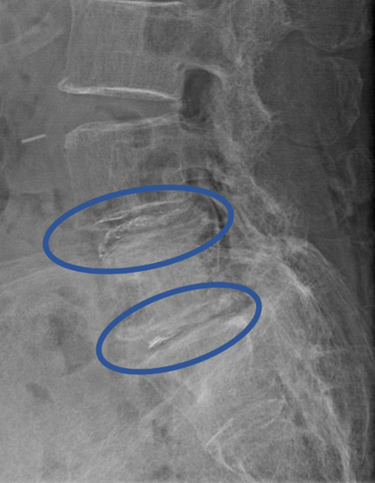

DiscoGelを入れた後の画像になります。

治療は 20分程度で終了

回復室で休憩後、歩いて帰院されました。